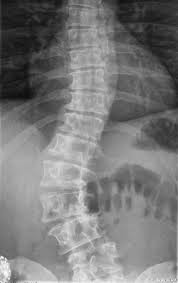

导读: 正常脊柱从背后看是直的,侧面看是呈S型的。脊柱侧弯在触摸脊柱时,常可发现脊柱异常弯曲或后凸,肩胛和背部不对称,高低不平。

导读: 云骨脊柱专家指出,椎体骨折可导致创伤性脊柱后凸畸形,主要发生在胸腰段。随着近年来交通事故的增加,胸腰段骨折病例明显增多。创伤所致后凸畸形已成为临床常见的病因,主要是脊柱受到屈曲或垂直压缩暴力。

导读: 特发性是脊柱畸形的较常见原因,主要是引起脊柱侧凸。从病因学上来讲,并不十分明确,但是和基因和遗传具有一定关系,此外还存在椎旁肌肉本身分布不平衡的原因。形态学是指椎体本身没有结构异常,椎体分隔正常,拥有